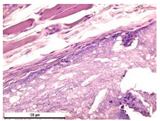

3.3.3. Morphological Study of Connective Tissue Capsules

Photographs of sections of the samples under study under various microscopy modes are shown in Table 8. Table 9 shows the distribution of the relative area of vessels (per 100 thousand µm2 of capsule area) for samples of magnesium calcium phosphate ceramics containing SPP, CA, and SPP_CA.

Sufficiently thick mature fibrous capsules with an increased content of vessels and pronounced inflammatory infiltration with a predominance of lymphocytes and neutrophils were mainly formed during implantation of samples of magnesium calcium phosphate ceramics of different compositions containing SPP. At the same time, the implant resorption was marginal with the penetration of single macrophages deep into the implant.

Only marginal resorption without penetration of macrophages deep into the implant was observed in the ceramic samples N0_CA and N0_SPP_CA. The introduction of single macrophages into the implant for composition N20, with a gradual increase for samples N40 and N60, was observed when newberyite appeared in the composition of the ceramics. Thinner capsules with less pronounced vascularization and inflammatory infiltration were formed during implantation of the magnesium calcium phosphate ceramic samples of different compositions with CA and SPP_CA. Compounds N40 and N60 actively germinated with fibroblasts.

The minimum relative area of vessels and capsule thickness is a characteristic of samples with CA, which confirms their biocompatibility. Biocompatibility increases in the range N0-N20-N40-N60 with all variants of setting inhibitors. Ceramics of the compositions N40_CA, N60_CA, N40_SPP_CA, and N60_SPP_CA have higher biocompatibility and resorption. The most mature thin fibrous capsule with moderate vascular content and weak inflammatory infiltration was observed. At the same time, intensive resorption of the implant by macrophages, giant multinucleated cells, and germination of ceramics by fibroblasts were observed.

Table 8. Section photos for the studied samples at different microscopy modes.

N0_LP0.7N20_LP0.7N40_LP0.7N60_LP0.7

SPPSLMCeramics 06 00011 i037Ceramics 06 00011 i038Ceramics 06 00011 i039Ceramics 06 00011 i040

PCMCeramics 06 00011 i041Ceramics 06 00011 i042Ceramics 06 00011 i043Ceramics 06 00011 i044

CASLMCeramics 06 00011 i045Ceramics 06 00011 i046Ceramics 06 00011 i047Ceramics 06 00011 i048

PCMCeramics 06 00011 i049Ceramics 06 00011 i050Ceramics 06 00011 i051Ceramics 06 00011 i052

CA_SPPSLMCeramics 06 00011 i053Ceramics 06 00011 i054Ceramics 06 00011 i055Ceramics 06 00011 i056

PCMCeramics 06 00011 i057Ceramics 06 00011 i058Ceramics 06 00011 i059Ceramics 06 00011 i060

SLM—standard light microscopy. PCM—phase-contrast microscopy. Hematoxylin-eosin, magnification 400×.